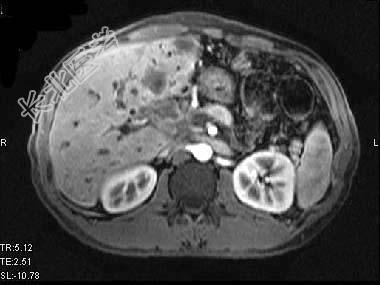

- 单项选择题根据所提供的图像,最可能的诊断是 ( )

A、肝囊肿

B、肝脓肿

C、先天性胆管扩张

D、胆管细胞癌肝内转移

E、以上都不是